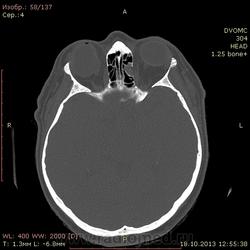

52 года. По направлению от невролога после травмы от 13.10. Правый глаз - посттравматические изменения(травма в детстве).

Интересует ваше мнение по поводу медиальной стенки левой глазницы - что за дефект? чего-то растет или последствия старой травмы или вариант нормы?

Или стенка все-таки без дефекта, а просто таким образом деформирована?

Считаю, что слева - это последствия "старой" травмы, т.н. взрывного (blowout) перелома медиальной стенки орбиты.